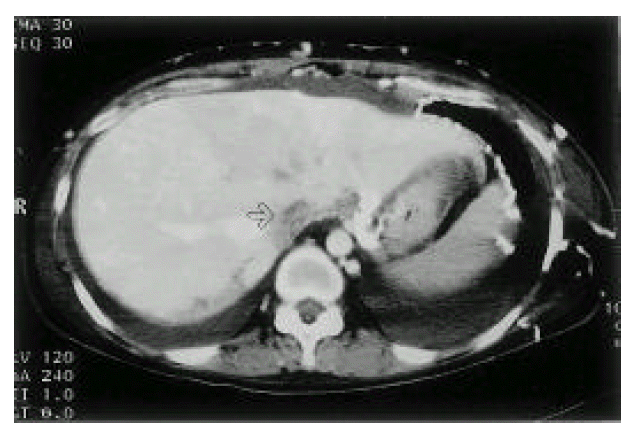

An X-ray film of the chest showed bilateral pleural effusion. Computed tomographic (CT) scan of the thorax (Fig. 3) demonstrated large amounts of bilateral pleural effusion and SVC occlusion with prominent collateral vessels at the chest wall, both axillary areas and within the mediastinum. Abdominal CT (Fig. 4) showed ascites and obliterated IVC, except for the short segment near the heart. Also, many collateral vessels were noted in the splenic hilar area, hepatosplenic ligament, retroperitoneum, mesentery, both perihilar areas of kidney, both paravertebral areas, perirectal area and the whole abdominal wall. Multiple round and wedge shaped, non-enhancing hypodense lesions suggest multiple liver infarction and diffuse hepatomegaly and mild splenomegaly were noted.

Fig. 4.

Abdominal CT. IVC is filled with low attenuate thrombus (arrow). Multiple collaterals are noted at the anterior abdominal wall, hepatogastric and hepatosplenic ligament area.